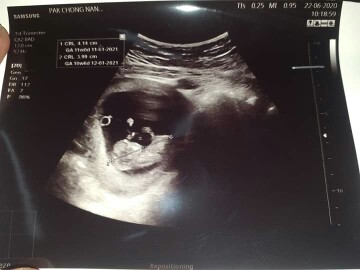

8 ม.ค.64 ยังไม่รู้เพศเลยจ้า 15 weeks

15มกราคม64 จ้า 13W ยังไม่รู้เพศเลย